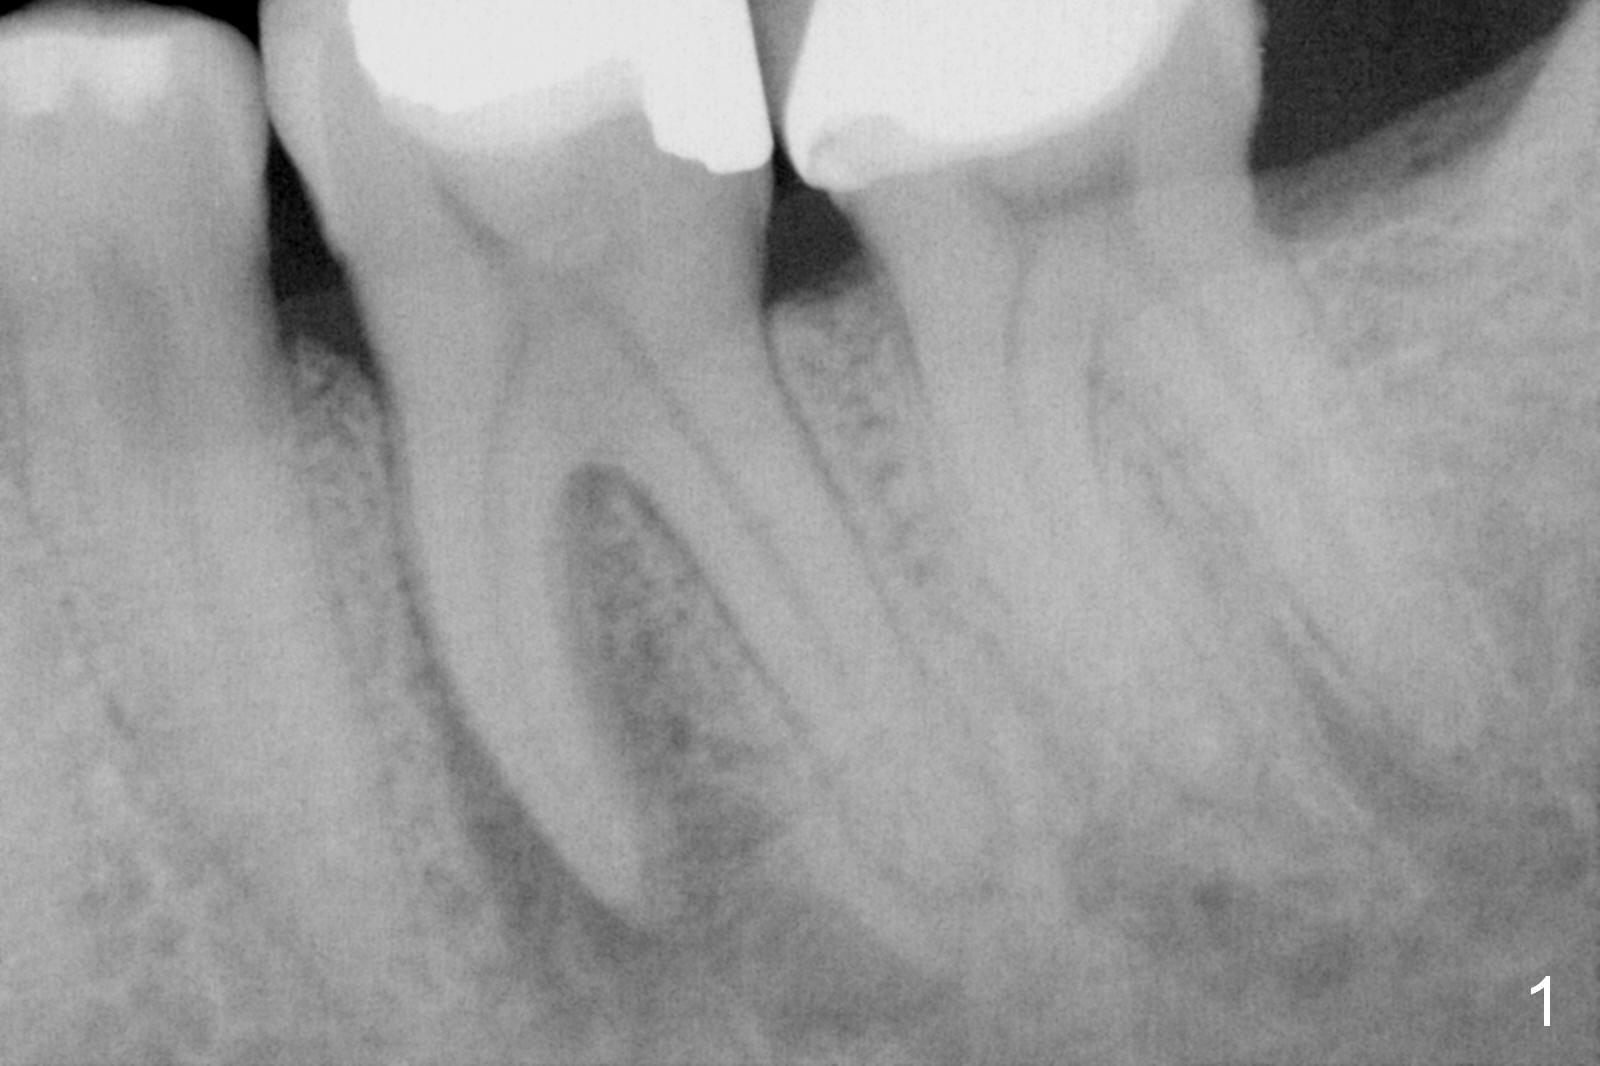

A 50-year-old man had pulpitis at #19 six years ago (Fig.1). RCT looks well filled (Fig.2). Recently he returns with severe toothache, involving the tooth #20 (Fig.3). There is no sign of crack tooth. Endo referral is recommended, but he would rather have it extracted first, since he is going to buy insurance near the end of the year for implant. He returns for extraction, since he could not sleep well the previous night. After block and periodontal ligament injection with two carpules of Lidocaine, extraction proves to be painful. A carpule of Marcaine is administered for block. While waiting for anesthesia to settle in, he suddenly agrees for immediate implant, since he had history of failure of bone graft after extraction at #30. The site needs regraft. The whole treatment takes two years.